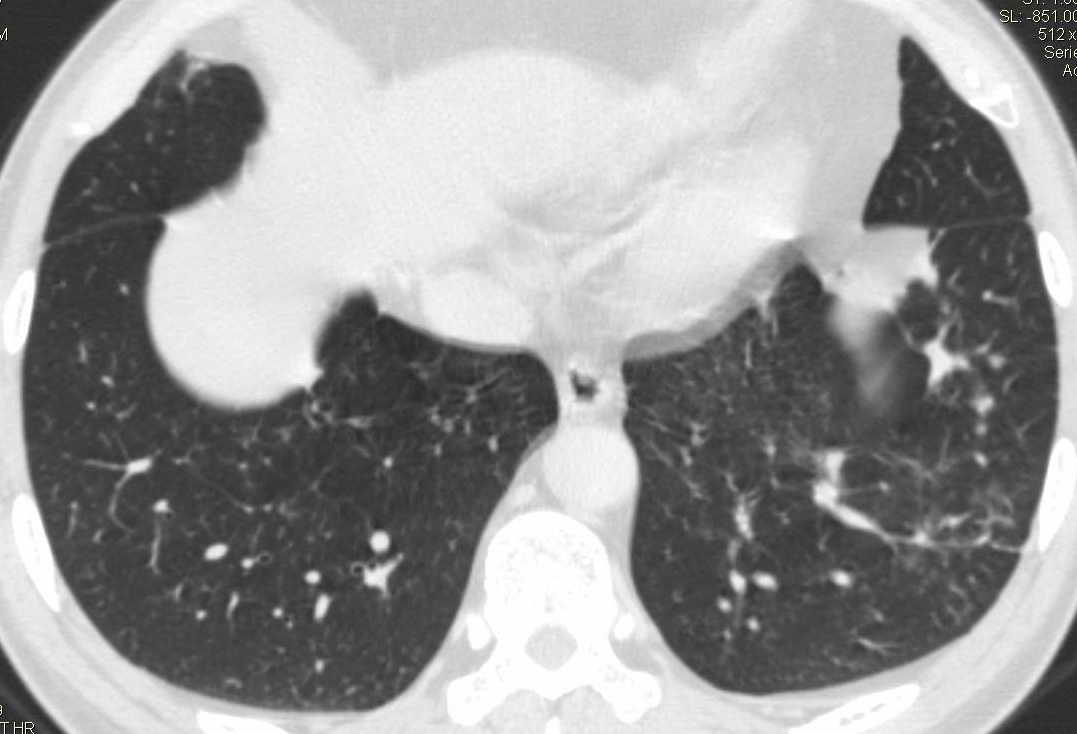

标题: CT15857:男性 58岁 咳痰带血 无发热 请各位大侠发表一下意见 [打印本页]

标题: CT15857:男性 58岁 咳痰带血 无发热 请各位大侠发表一下意见

两肺下叶肺纹理增多、增粗并呈“树芽状”改变。支气管扩张呈囊状,部分呈柱状改变。其周围可见散在的斑片样及条索样密度增高影,右肺下叶近叶间胸膜可见一形态不规则的高密度结节影,并与胸膜粘连。

考虑:支扩并发感染。

双肺多发炎性病灶,结核可能性大,建议抗炎治疗复查.右肺下叶前基底段结节灶,高度警惕肺癌可能

双肺间质性改变(间质纤维化?)伴支扩。右肺下叶有毛刺的小结节,考虑周围型肺癌可能性。